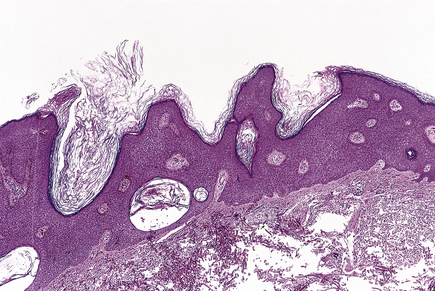

Seborrhoeic warts/keratoses are much more common in the elderly and, despite their name, have nothing to do with sebaceous glands. They are also called basal cell papillomas but seborrhoeic wart/keratosis is the preferred name to avoid confusion with the term basal cell carcinoma. They are dark, greasy-looking (hence ‘seborrhoeic’) nodules with an irregular surface (Fig. 24.11). They can occur on most parts of the skin surface and rarely turn malignant. Histologically they consist of a proliferation of cells with similar appearances to the basal cells in the epidermis (Fig. 24.12). They have a very convoluted surface with keratin tunnels extending deeply from the surface inwards (horn cysts). In some cases they may become inflamed, due to irritation or attempts by the body to remove the lesion (regression). Although they have little biological significance, they are often removed for cosmetic purposes or to exclude melanoma. In one very rare condition a sudden, widespread, pruritic crop of these lesions may be a sign of internal malignancy, usually in the gastrointestinal tract (the sign of Leser–Trélat).

image

Fig. 24.11 Seborrhoeic wart/keratosis (basal cell papilloma). A symmetrical, benign lesion. It may occur anywhere on the skin and is commoner in the elderly.

Fig. 24.12 Seborrhoeic wart. This shows a proliferation of basal cells with thickened epidermis (acanthosis) and projection above the surface (papillomatosis). The lesion seems ‘stuck’ on the dermis.